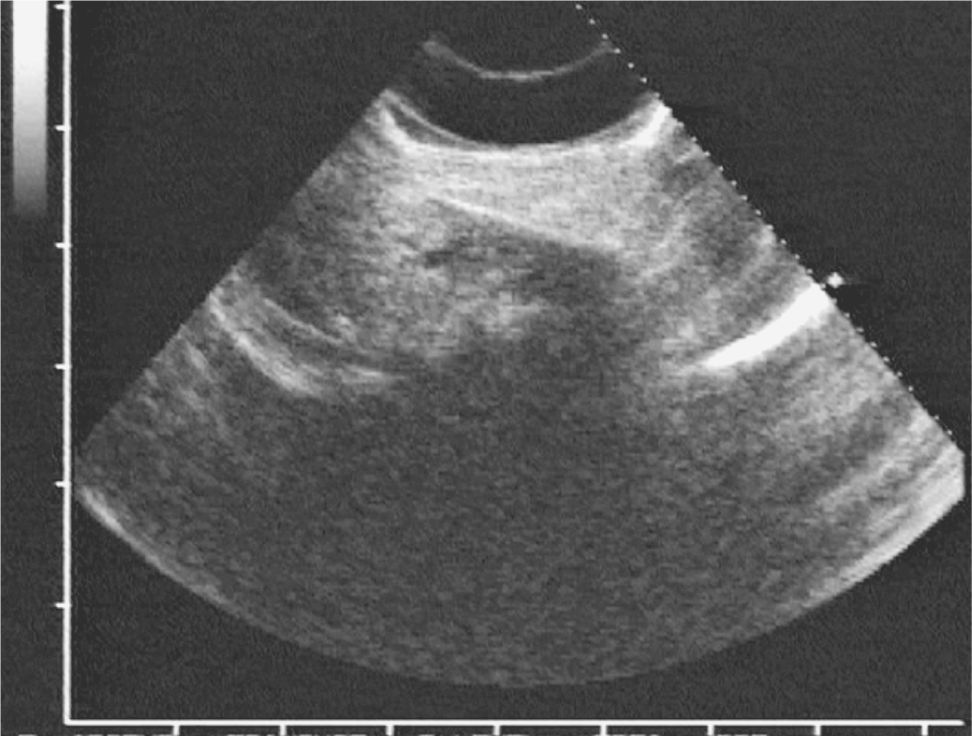

Benign gallbladder diseases Imaging techniques and tips for Non Radiopaque Calculi Urolithiasis refers to the presence of calculi anywhere along the course of the urinary tracts. Asymptomatic kidney stones should be followed with serial imaging, and should be removed in case of growth, symptoms, urinary obstruction, recurrent infections, or lack of. For the purpose of the article, the terms urolithiasis,. They may cause pain, nausea, vomiting, hematuria, and, possibly, chills and. Non Radiopaque Calculi.